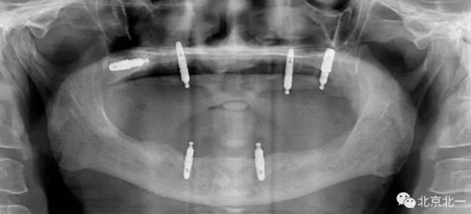

圖一:球帽覆蓋義齒

1.png